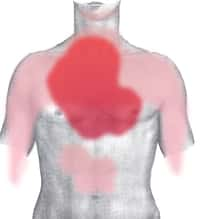

Localisation des principaux pouls : les points névralgiques

Les principaux points de mesure du pouls reflètent la pulsation des artères majeures. Ce sont le poignet (artère radiale), le cou (artère carotide), l'aine (artère fémorale), le pli du coude (artère humérale), derrière le genou (artère poplitée) et à la chevillecheville (pouls tibial postérieur).